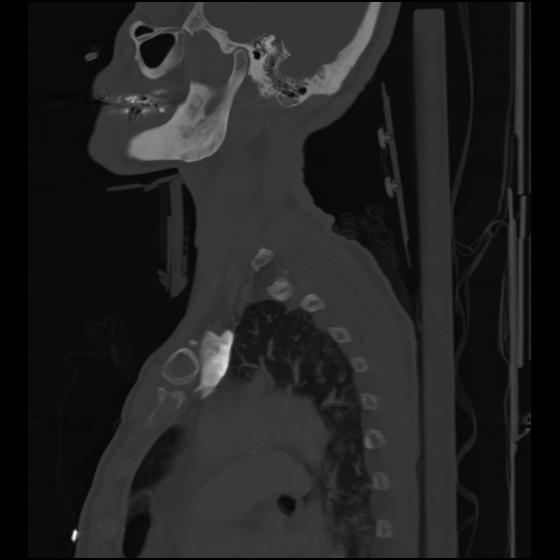

24 ANGIO,CE,Sag-MIP,5.000,ANGIO,Sag-MIP,